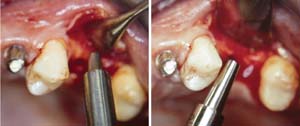

A 53-year-old female was referred for evaluation of a fracture of tooth No. 24. The tooth had been treated endodontically 5 years prior. The radiograph revealed a complete fracture of the tooth involving the crown (Figure 12). Tooth extraction and immediate placement of a an implant that was 10 mm in length and 3.75 in diameter was planned.

At the time of surgery, the tooth was extracted without harvesting any mucosal flap because the implant site was prepared by means of a pilot drill bur (Figure 13) and alternating osteotomes (Figure 14A and Figure 14B). The implant was positioned and showed primary stability. The implant was loaded 2 days after surgery. Then, splinted PFM crowns supported by custom gold abutments were delivered. At 6 months posttreatment, the radiograph revealed no bone resorption and the clinical result was optimal (Figure 15A and Figure 15B).

Figure 13  The drill bur was used to start the implant site preparation.

Figure 14A and Figure 14B Alternating osteotomes were used to prepare the implant site.

Figure 13

Figure 14a  Alternating osteotomes were used to prepare the implant site.

Figure 14a

Figure 14b  Alternating osteotomes were used to prepare the implant site.

Figure 14b